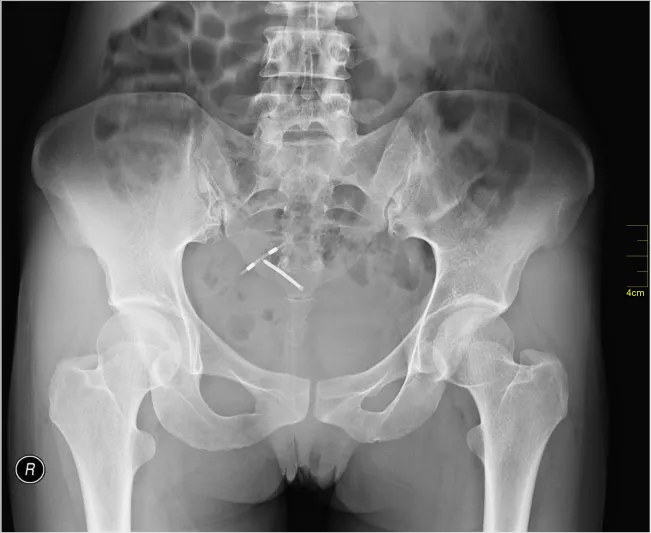

وذلك ما حدث لامرأة مقيمة عقب إجرائها لعملية ولادة قيصرية بأحد المستشفيات الخاصة بمدينة الدمام حيث تبين وجود جسم غريب بأمعائها وذلك من خلال التصوير المقطعي، بعدما عانات ألام في بطنها.

حيث تم العثور على قطعة من القماش داخل أمعائها، استمرت في بطنها أربعة أشهر، وبعد إجراء العملية كانت تشعر بآلام في بطنها، كما بدأت تظهر عليها أعراض صحية، مثل القيء، وعدم قدرتها على الأكل، وبعمل آشرة صوتية، تبين وجود تضخم بالأعضاء الداخلية، والتصاق بالأمعاء، وانسداد، وبعمل أشعة مقطعية وأشعة X ، بينت وجود قطعة شاش بالبطن من مخلفات العملية السابقة